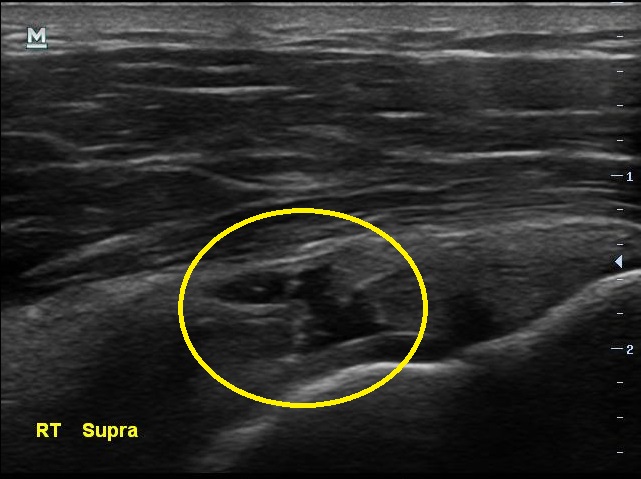

통증이 있지만 운동을 멈추지 않았다는 남자분.... 결과는 생각보다 나빴습니다. 초음파 검사상에서 이두박근의 장두에 염증이 보였고 극상근 힘줄에는 부분파열 소견이 보이고 있었습니다.

초음파 검사 결과 3개월전에 비해 극상근 힘줄의 파열 정도가 더 심해져있습니다.